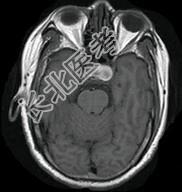

- 单项选择题男性,55岁, 头痛一年余,两个小时前突然出现剧烈头痛, MRI检查如图所示,最可能的诊断为 ( )

E、动脉瘤